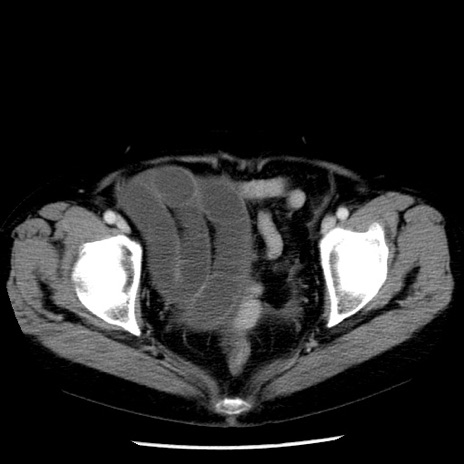

症例13(横断像)

【症例】70歳代女性

【主訴】腹痛、嘔吐

【現病歴】15時間程前(昨晩)より腹痛あり。今朝になっても症状の改善なく、嘔吐あり。腹痛も増悪あり、救急外来受診。

【既往歴】子宮癌全摘術後

【身体所見】意識清明、BP 121/72mmHg、P 74bpm、SpO2 100%(RA)、腹部:平坦・軟、腸雑音ほぼ聴取せず。下腹部・心窩部・臍左上に圧痛あり。反跳痛なし。

【データ】WBC 10600、CRP 0.15